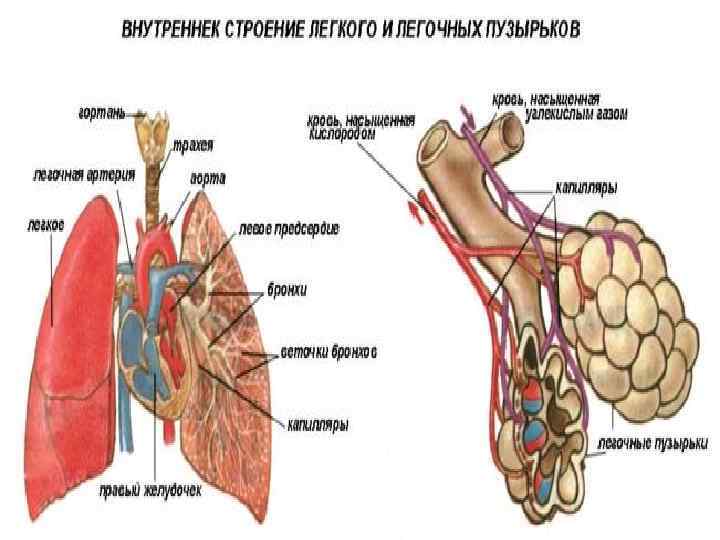

Роль легких в метаболических процессах